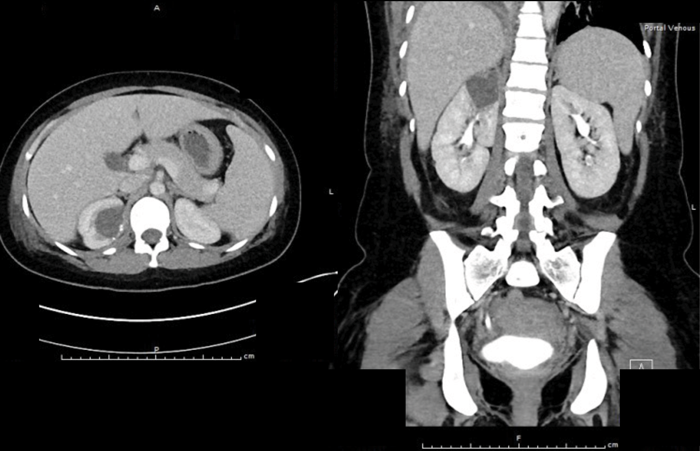

A previously fit and well 65-year-old man presents with acute onset, left loin pain and non-visible haematuria. He underwent a CT KUB suspecting renal stones (no stones seen), therefore he had a subsequent contrast CT scan. These images are shown below:

There is diffusely marked hypo perfusion throughout the right kidney. The left kidney demonstrates an infarction of the posterior and superior segments of the left kidney.